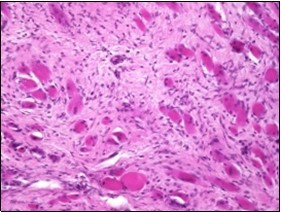

On microscopy, a collagen- rich, minimally cellular, fibrotic soft tissue nodule is exemplified which simulates a scar or conventional fibroma. The neoplasm is comprised of uniform, plump, fibroblastic or myo-fibroblastic cells encompassed in a collagen-rich stroma with infiltration and entrapment of skeletal myocytes 5, 6. Cogent histological examination depicts replacement of muscle fibres and muscle mass with fascicles of fibrous tissue comprised of mature fibroblastic cells, thereby conferring fibrosis 6. Figure 1, Figure 2, Figure 3, Figure 4, Figure 5, Figure 6, Figure 7, Figure 8.

Figure 1.Fibromatosis colli depicting bundles of fibroblasts and myo-fibroblasts intermixed with a collagenous stroma and entrapped myocytes 9.